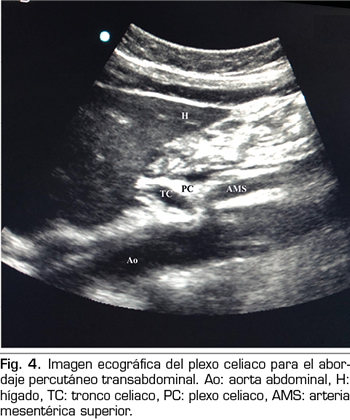

Figura 4